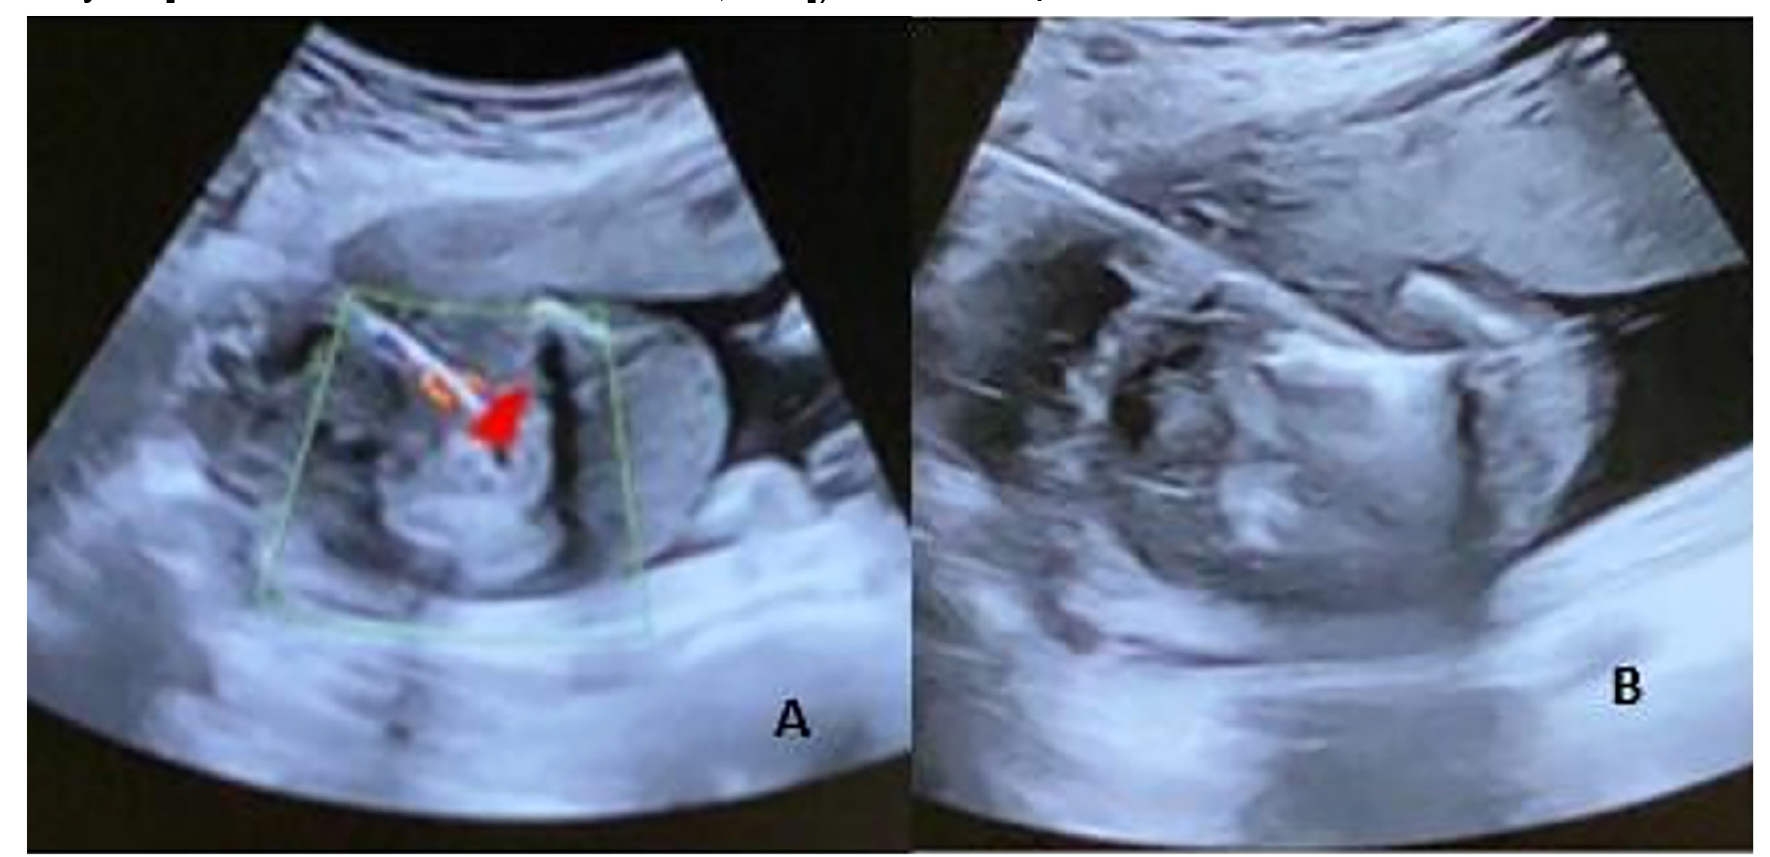

Under ultrasound guidance, the optimal puncture site was identified and a small skin incision made. The antenna was then inserted percutaneously into the affected fetus’s abdominal cavity, with the trocar advanced to the cord insertion site while avoiding placental penetration (figure 2a). MWA was performed at 100 W for 3 min per cycle (based on the manufacturer’s recommendation protocol) to create an approximately 15 mm radius ablation zone around the umbilical cord insertion.

Figure 2. A) The image demonstrates the percutaneous insertion of the antenna into the abdominal cavity of the affected fetus under ultrasound guidance. B) The echogenic zone represents coagulation necrosis following microwave ablation (MWA), visible as an ultrasound sign.

Fetal bradycardia occurred universally during initial ablation. Doppler ultrasound confirmed complete cessation of target fetal circulation; additional cycles were administered if necessary. The procedure’s completion was marked by visualization of an echogenic coagulation zone indicating necrosis (figure 2b). Finally, the fetal heart rate of the surviving fetus was checked, and in the case of polyhydramnios, amnioreduction was performed.